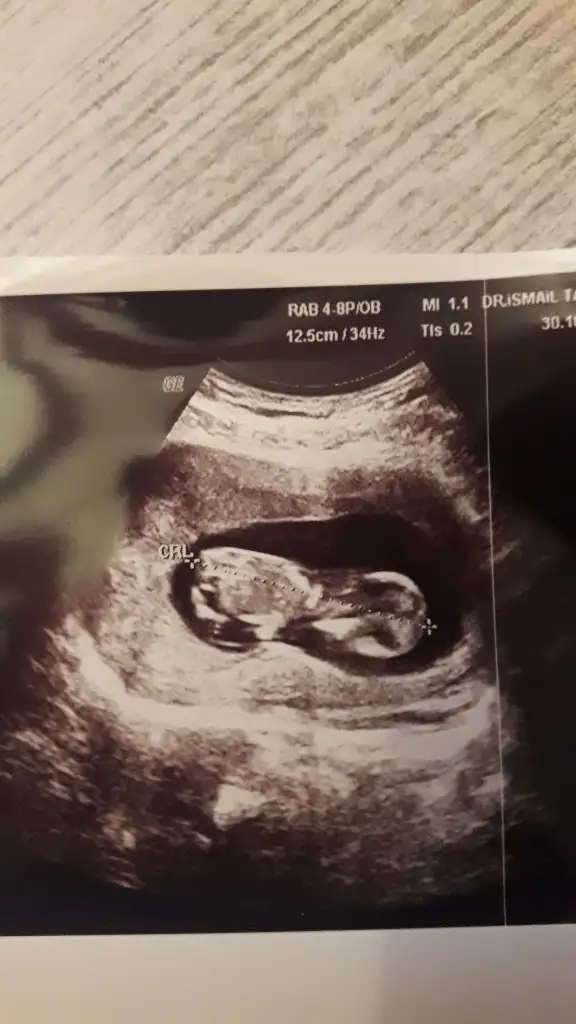

Merhaba bizim bebiş ters duruyor secde pozisyonunda ultrasona göre 12+3 benim bebişim içinde bir tahminde bulanabilirmisiniz rica etsem.

Cinsiyetimiz nedir sizce :)